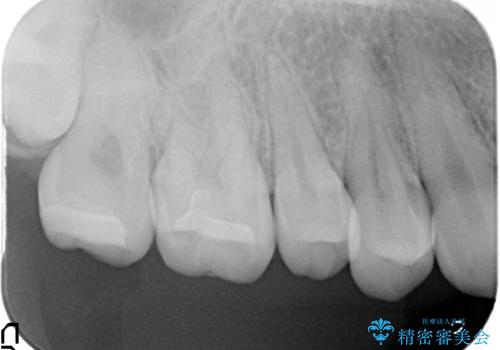

- 右上奥歯の古い樹脂と銀歯をセラミックにやり替えた症例です。

右上67の樹脂及び銀歯を除去後、セラミックインレーにて修復を行いました。